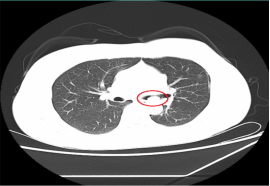

近日,一位患支氣管腫瘤患者到我院呼吸內科治療,檢查時,其腫瘤幾乎已經完全堵塞氣管管腔,若不及時手術,隨時可能發生呼吸衰竭。

情況危急,醫生立即為其抽取動脈血化驗并給予高流量吸氧等,但患者呼吸困難的癥狀緩解不明顯,必須及時將腫瘤切除。“如果按照傳統的手術方式,需將患者氣管切開,組織損傷性高、流血量多。由于患者腫瘤貼近降主動脈,切除過程中將伴有大出血的風險。”劉碧翠說,隨著我院內鏡技術的發展,對于這樣的重癥患者,可以利用呼吸內鏡迅速切除腫瘤,清理氣道內局部的壞死組織、分泌物并予以止血處理。

科室介入團隊經過精心準備后,立刻為患者實施內鏡介入手術,將氣道內腫物切除干凈。手術僅用時2小時,患者沒有發生大出血,很快便恢復出院。此次手術的成功開展,充分體現了呼吸內科對此類疑難危重氣道疾病患者的救治能力。